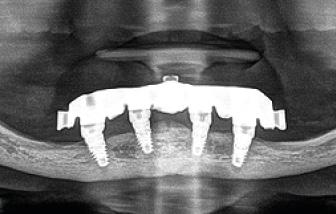

CBCT revealed the following findings:

LL8: IAC was running buccal to roots of LL8 which had 3 roots (Fig 2).

RL8: IAC was seen running between the buccal root which was hooked mesially and lingual roots at its apex, vulnerable to surgical injury (Fig 3).